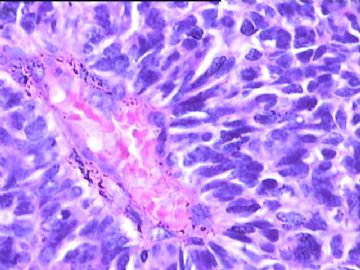

女,34y,头痛一月,右额叶占位:5*5*4cm。囊性区域,4cm。大体:3.5x3x1cm灰白间暗褐色组织一堆,质嫩。临床诊断1:胶质瘤,2:血管母细胞瘤。

本人县级医院头颅手术少,考虑胶质母细胞瘤。大家指导指导。

胶母

同意胶质母细胞瘤。细胞异型、坏死、核分裂、血管内皮肿胀增生均可见到。

This is certainly a WHO grade IV malignant neoplasm. While most likely a glioblastoma, I would carefully rule out PNET by staining for GFAP and neuronal markers such as synaptophysin, NeuN and NSE. Rarely, PNET may shows marked pleomorphism and indistinguishable from glioblastoma on HE stain.

同意马老师的意见,该肿瘤从形态及年龄来看考虑PNET或GBM,须标记Syn、NSE、S-100、NeuN和GFAP来鉴别。

结合图片细胞形态特点考虑胶质母细胞瘤,组化标记排除其他